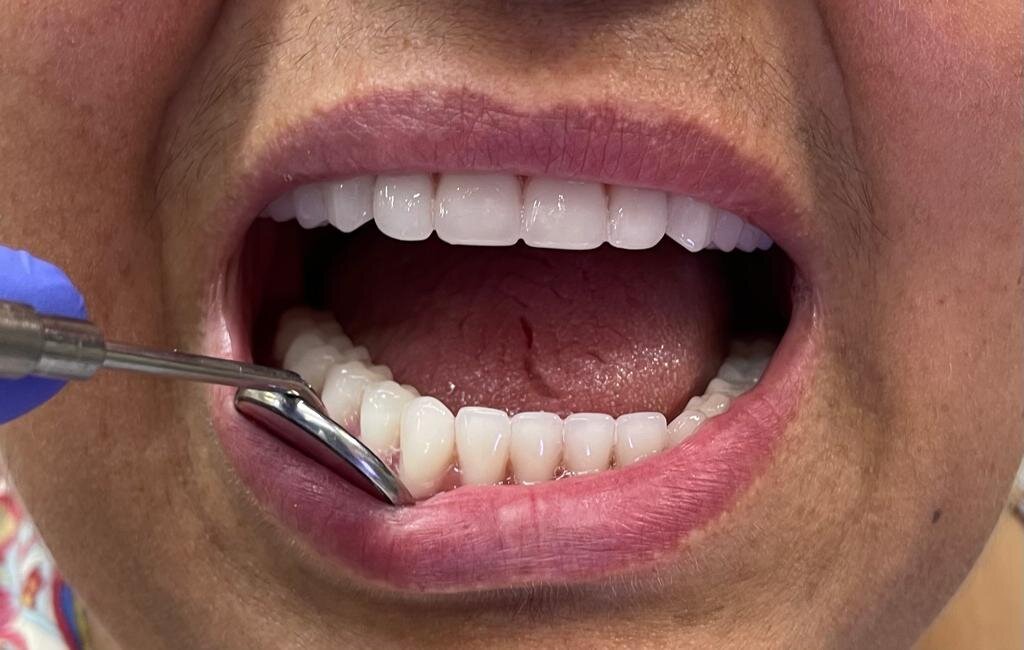

Фотогалерея